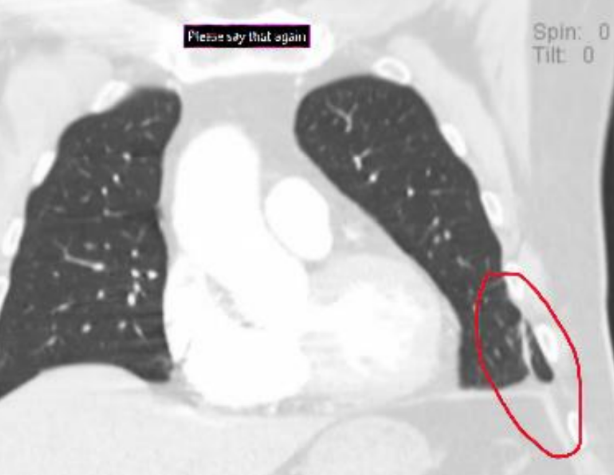

2006년 또다시 병원으로 이송된 청페이밍은 그곳에서 탈출해 2020년 미국으로 갔다. 미국 병원에서 검진을 받은 결과 폐와 간의 일부가 사라진 사실이 확인됐다. 현재 뉴욕에 살고 있지만 끊임없이 살해 협박에 시달리고 있다.